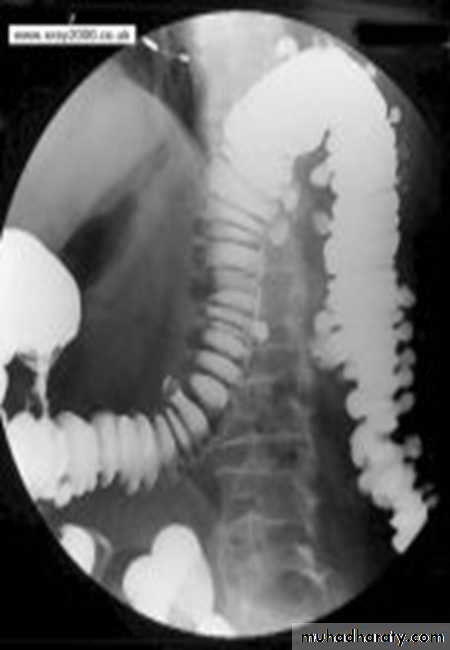

Ba enema

• Morphological types:• 1_ Ulcerative : give rise to irregularity of the colon with ulceration.

• 2_ Constrictive or infiltrative ( Annular ) type :

• a- Constant narrowing .

• b-Shouldering sign, apple core sign .

• c- Destruction of mucosa at narrow area .

• d- Double track due to fistula .

• e- In severe constriction ; stoppage of Ba. Flow with proximal dilatation .

3_Proliferative type : give rise to :

a- Large , constant filling defect with irregular margin .

b- Destruction of mucosa .

c- Intestinal obstruction

apple core lesion in the descending colon

Multiple lesions are seen in the liver and spleen consistent with metastases